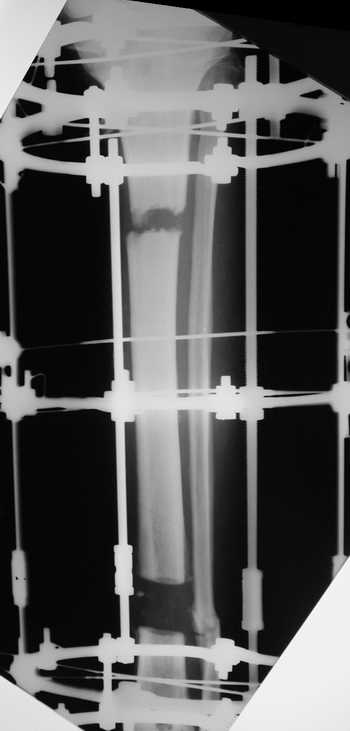

Еще один пример.

Мужчина, 33 года, резекция б\б кости по поводу остеомиелита после открытого перелома. Стандартная методика билокального остеосинтеза (рис 1 и 2). В конце удлинения выявилось неудовлетворительное взиморасположение перемещенного фрагмента и дистального отломка (рис 3). Планирование (рис 4).

Адаптация отломков гексаподом за 5 дней (рис 5). Замена гексапода на обычные штанги (рис 6 и 7)